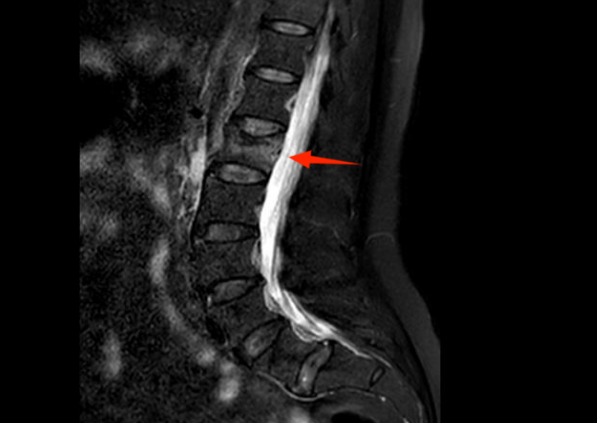

家人急忙将她送到昆山市中医医院,检查结果让她难以置信:第一腰椎骨折。“这不是意外摔伤,而是典型的骨质疏松性骨折。” 脊柱骨科陈吉主任中医师指着骨密度报告解释,“您的骨密度 T 值低至 - 2.8,远低于正常标准,血钙和维生素 D 也严重不足,骨骼已经脆到扛不住打喷嚏时腹压增加的力量。”

图片

▲患者CT影像显示:第一腰椎骨折